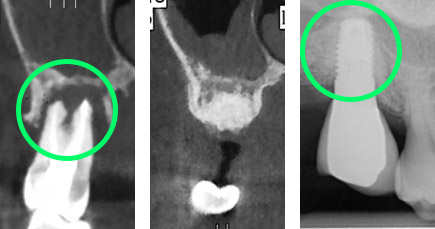

Le reconstruction des segments osseux édentés